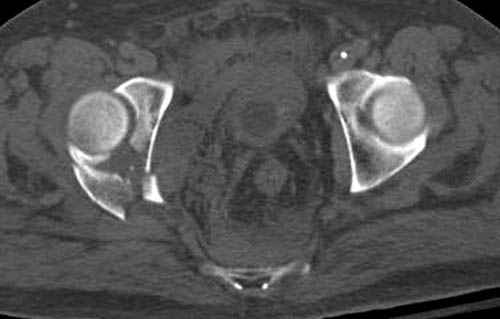

Дополнительно имеется перелом ацетабулума: задняя

колонна с полупоперечным переломом, и переломы костей лица.

На седьмой день зафиксирован перелом ацетабулума через задний доступ. Перед операцией для профилактики DVT, IVC фильтер, также получает Lovenox.

Извиняюсь за качества снимков, обычный больной в 300 фунтов, портативным ренген аппаратом не пробить.